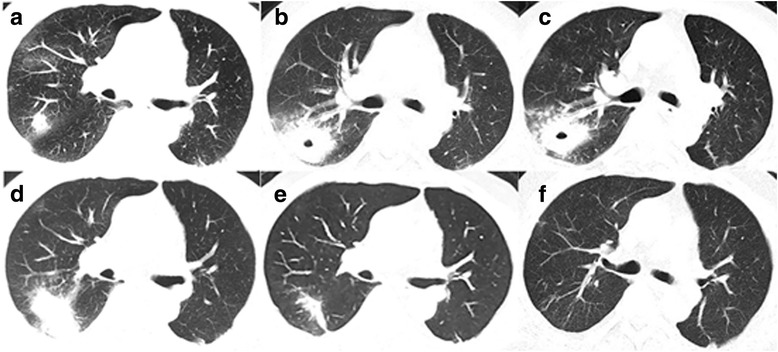

Fig. 2.

The patient’s pulmonary CT scan showed changes of the lesion during course of disease. a Right upper lobe nodule revealing recurrence of lung cancer confirmed by pathology (2016-3-21); b Right lung lesion became larger accompanied by an empty cavity after chemotherapy (2016-5-4); c No significant change of the right lung lesion after levofloxacin and cefepime treatment (2016-5-18); d No significant change of the right lung lesion after praziquantel treatment (2016-9-5); e Absorbed lesions after metronidazole treatment (2016-12-26); f No recurrence of amoeba during 6-month follow-up (2017-06-06)

The patient was diagnosed left lower lung adenocarcinoma (pT1N0M0, Ia) in 2012, and then received surgical resection without chemotherapy. In March 2016, the patient began to develop dry cough, without fever, chest pain, hemoptysis and night sweats. Chest computed tomography (CT) scan was performed and revealed multiple lung nodules, enlarged right hilar and mediastinal lymph nodes (Figs. 1 and 2a). Suspecting metastatic malignant tumor, further bronchoscopy biopsy was then performed, and the pathological diagnosis reported non-mucoid adenocarcinoma. At that time, the patient was diagnosed left lung adenocarcinoma recurrence (rT4N2M1, Ia), and underwent “pemetrexed + cisplatin” chemotherapy on March 23 and April 13. However, the patient still experienced cough, with white sputum and no hemoptysis. On May 4, the second chest CT showed that the right upper lobe nodules became larger in size, accompanied by an empty cavity while the remaining multiple nodules in both lungs have been absorbed (Fig. 2b). At that time, the right upper lobe lesion was considered infectious lesion and repeated sputum smear and culture were taken, all coming back negative, including acid-fast staining. The patient was then empirically treated with levofloxacin and cefepime for 7 d, but his symptoms didn’t relieve. On May 18, there was no change of the upper lobe lesion in a reviewed chest CT (Fig. 2c). The bronchoscopy biopsy was performed again and neither malignant tumor cells nor suspected pathogens were found. Moxifloxacin was administered for 7 d with no symptoms relief.

There was still no significant change of the right lung lesion in a reviewed chest CT examination (Fig. 2d). Still suspecting a possible parasite infection, the lung biopsy specimens were sent to Shanghai Medical College Institute of Parasitology for consultant. Amoebic trophozoites ingesting erythrocytes were found under the microscope (Fig. 3), and the serum antibody of amoebic trophozoites [3] was 1:64 (Additional file 2: Figure S1). The enteroscope examination showed multiple polyps. The PCR test for Entamoeba gingivalis was negative. The patient was diagnosed as pulmonary amebiasis and he was given metronidazole 0.5 bid ivgtt for 11 days, and then metronidazole 0.4 tid po before discharge. The patient’s cough gradually reduced and lesions were significantly absorbed by reviewed chest CT on December 26 (Fig. 2e). On June 6 2017, reviewed lung CT showed that the lesions were completely absorbed (Figs. 2f and 4).